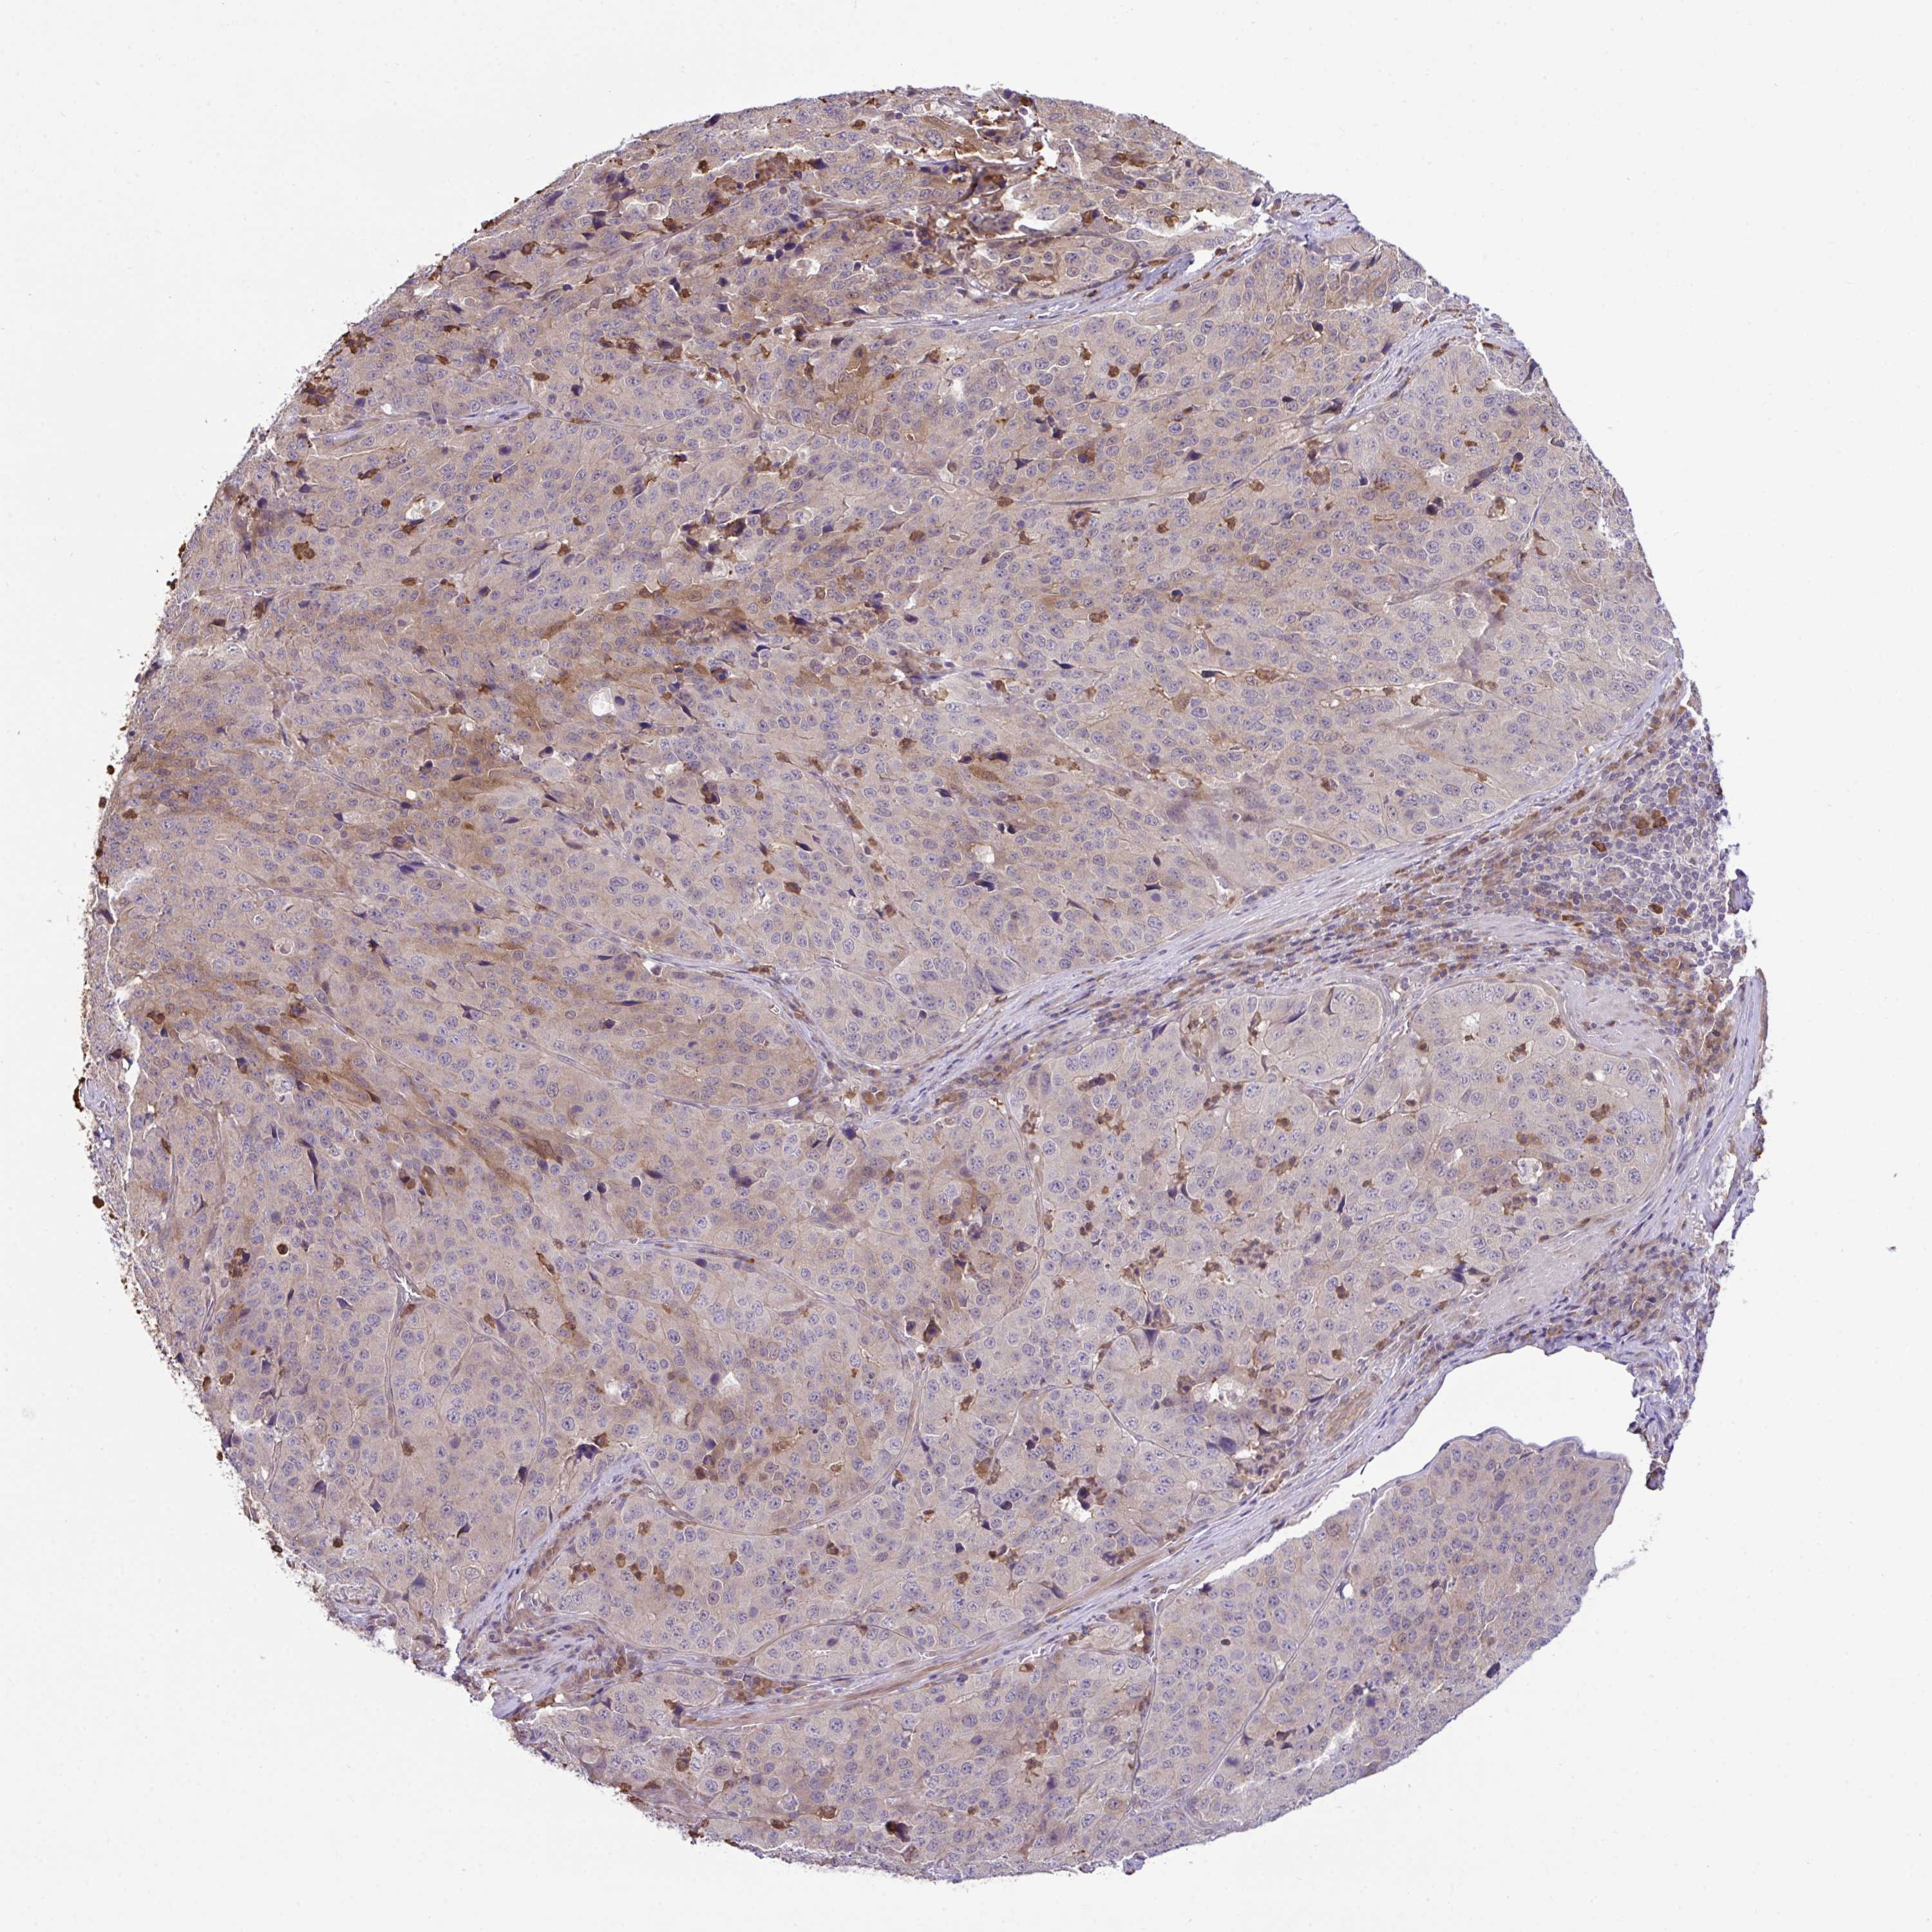

STOMACH CANCER - Protein expressioni

A mouse-over function shows sample information and annotation data. Click on an image to view it in a full screen mode. Samples can be filtered based on level of antibody staining by selecting one or several of the following categories: high, medium, low and not detected. The assay and annotation is described here.

Note that samples used for immunohistochemistry by the Human Protein Atlas do not correspond to samples in the TCGA dataset.

Antibody stainingi

Antibody staining in the annotated cell types in the current human tissue is reported as not detected, low, medium, or high, based on conventional immunohistochemistry profiling in selected tissues. This score is based on the combination of the staining intensity and fraction of stained cells.

Each image is clickable and will lead to virtual microscopy that enables deeper exploration of all samples and also displays staining intensity scores, fraction scores and subcellular localization as well as patient and tissue information for each sample.

Antibody HPA053730

Antibody HPA058604

Staining

High

Medium

Low

Not detected

Intensity

Strong

Moderate

Weak

Negative

Quantity

>75%

75%-25%

<25%

None

Location

Nuclear

Cytoplasmic/membranous

Cytoplasmic/membranous,nuclear

Adenocarcinoma, NOS